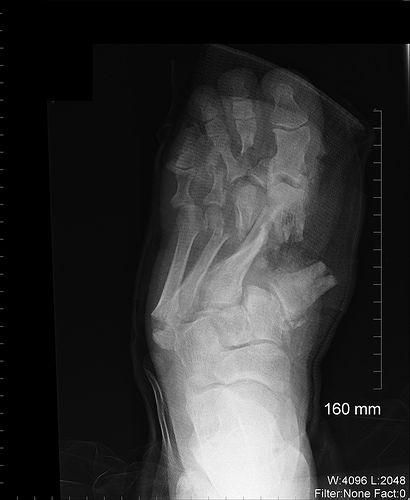

Перелом ноги